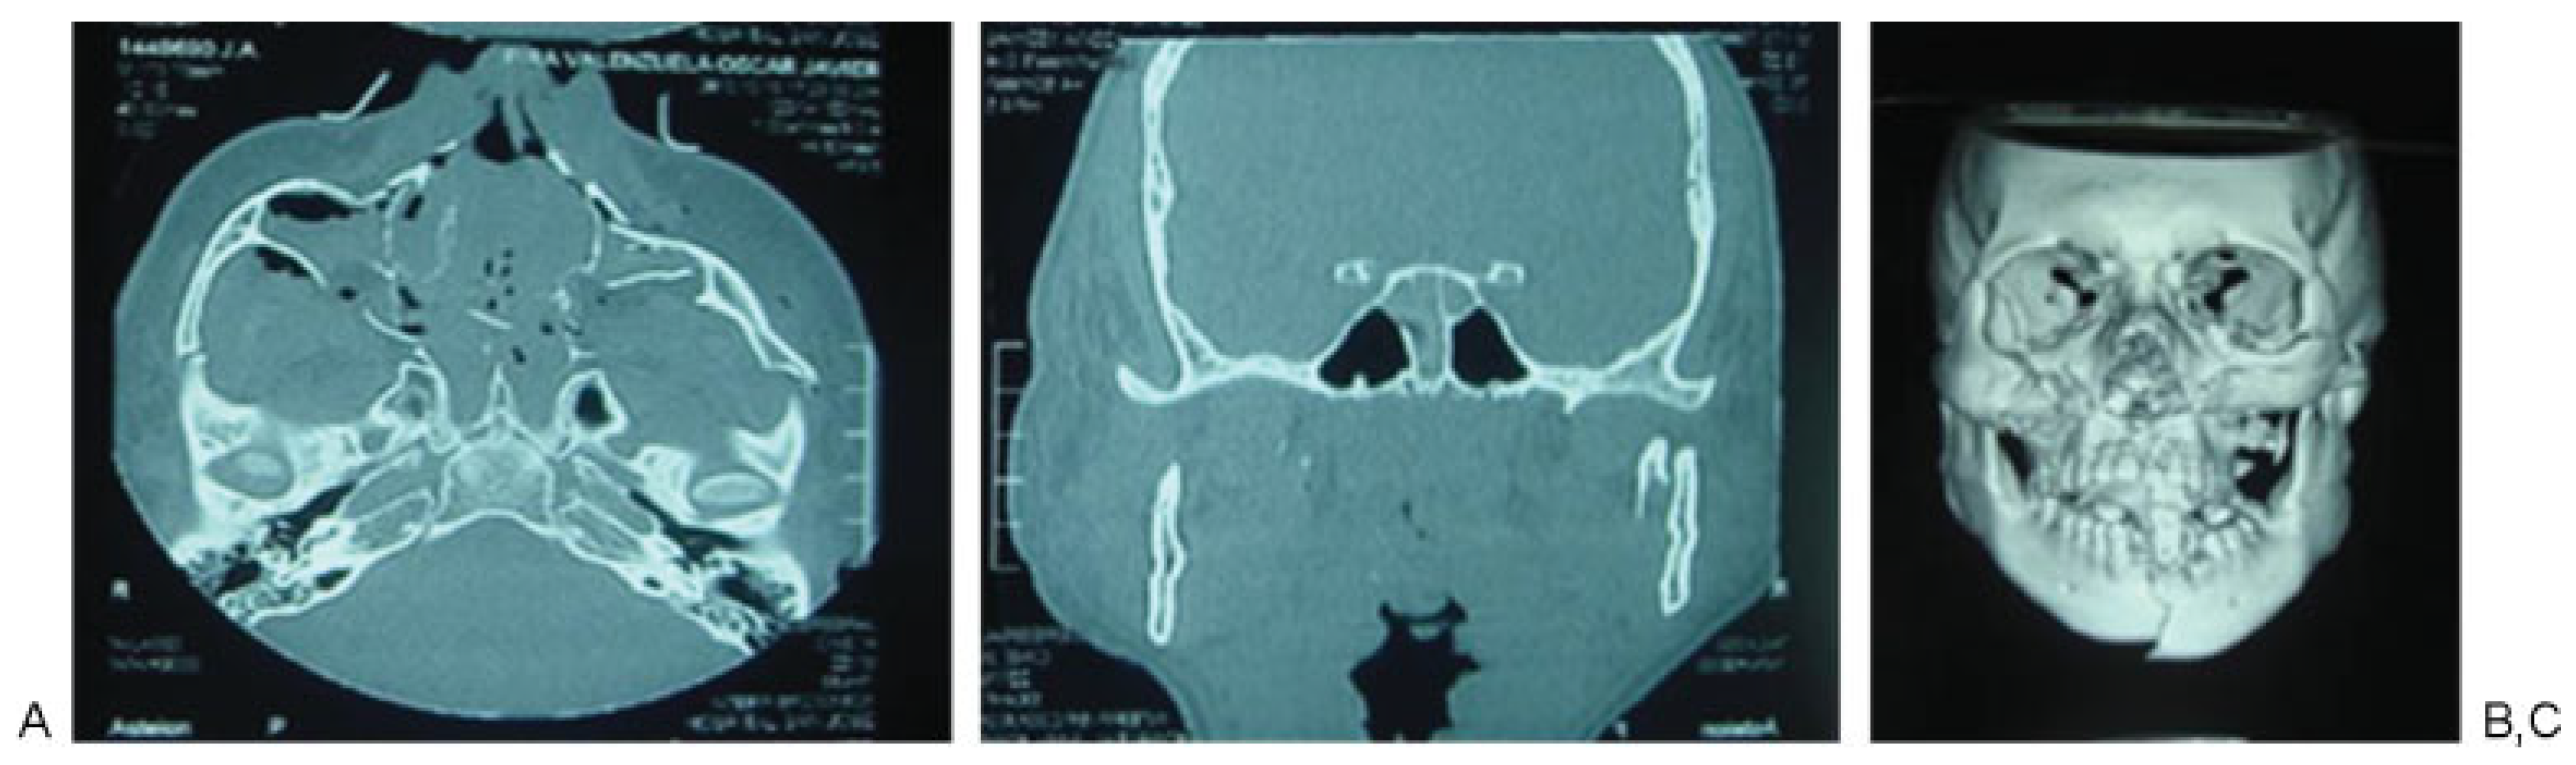

Figure 4. Patient 3: slightly displaced malar fracture in a patient with medium energy trauma, (A) presence of fracture at the level of the zygomatic arch, (B and C) fracture at the lateral wall of the sphenoid bone and orbital fracture associated.

According to Manson’s classification, 17.9% (n ¼ 38) of the trauma in the group corresponded to high-energy trauma, followed by medium-energy trauma at 33.5% (n ¼ 71) and low-energy trauma at 48.6% (n ¼ 103). Among the patients with high-energy trauma, 31.5% (n ¼ 12) had combined fractures of the sphenoid bone and sphenoid sinus and 31.5% (n ¼ 12) had sphenoid sinus fractures only. In contrast, 1.4% (n ¼ 3) of patients with middle-energy trauma had sphenoid bone fractures, 5.6% (n ¼ 4) of the patients had sphenoid sinus fractures, and 4.2% (n ¼ 3) of the patients had sphenoid bone and sphenoid sinus fractures. In the low-energy trauma group, only 1 patient presented sphenoid sinus fracture (0.97%; Table 3; Figure 2, Figure 3 and Figure 4).